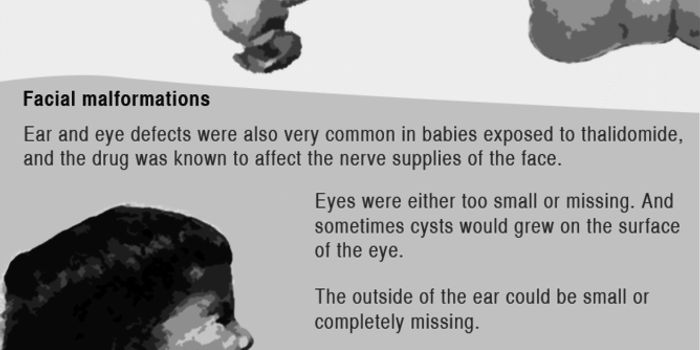

SEP 27, 2017VideosWhat cannot kill can still inflict terrible harm - this is what makers of the thalidomide drug found out too late. Thali ...